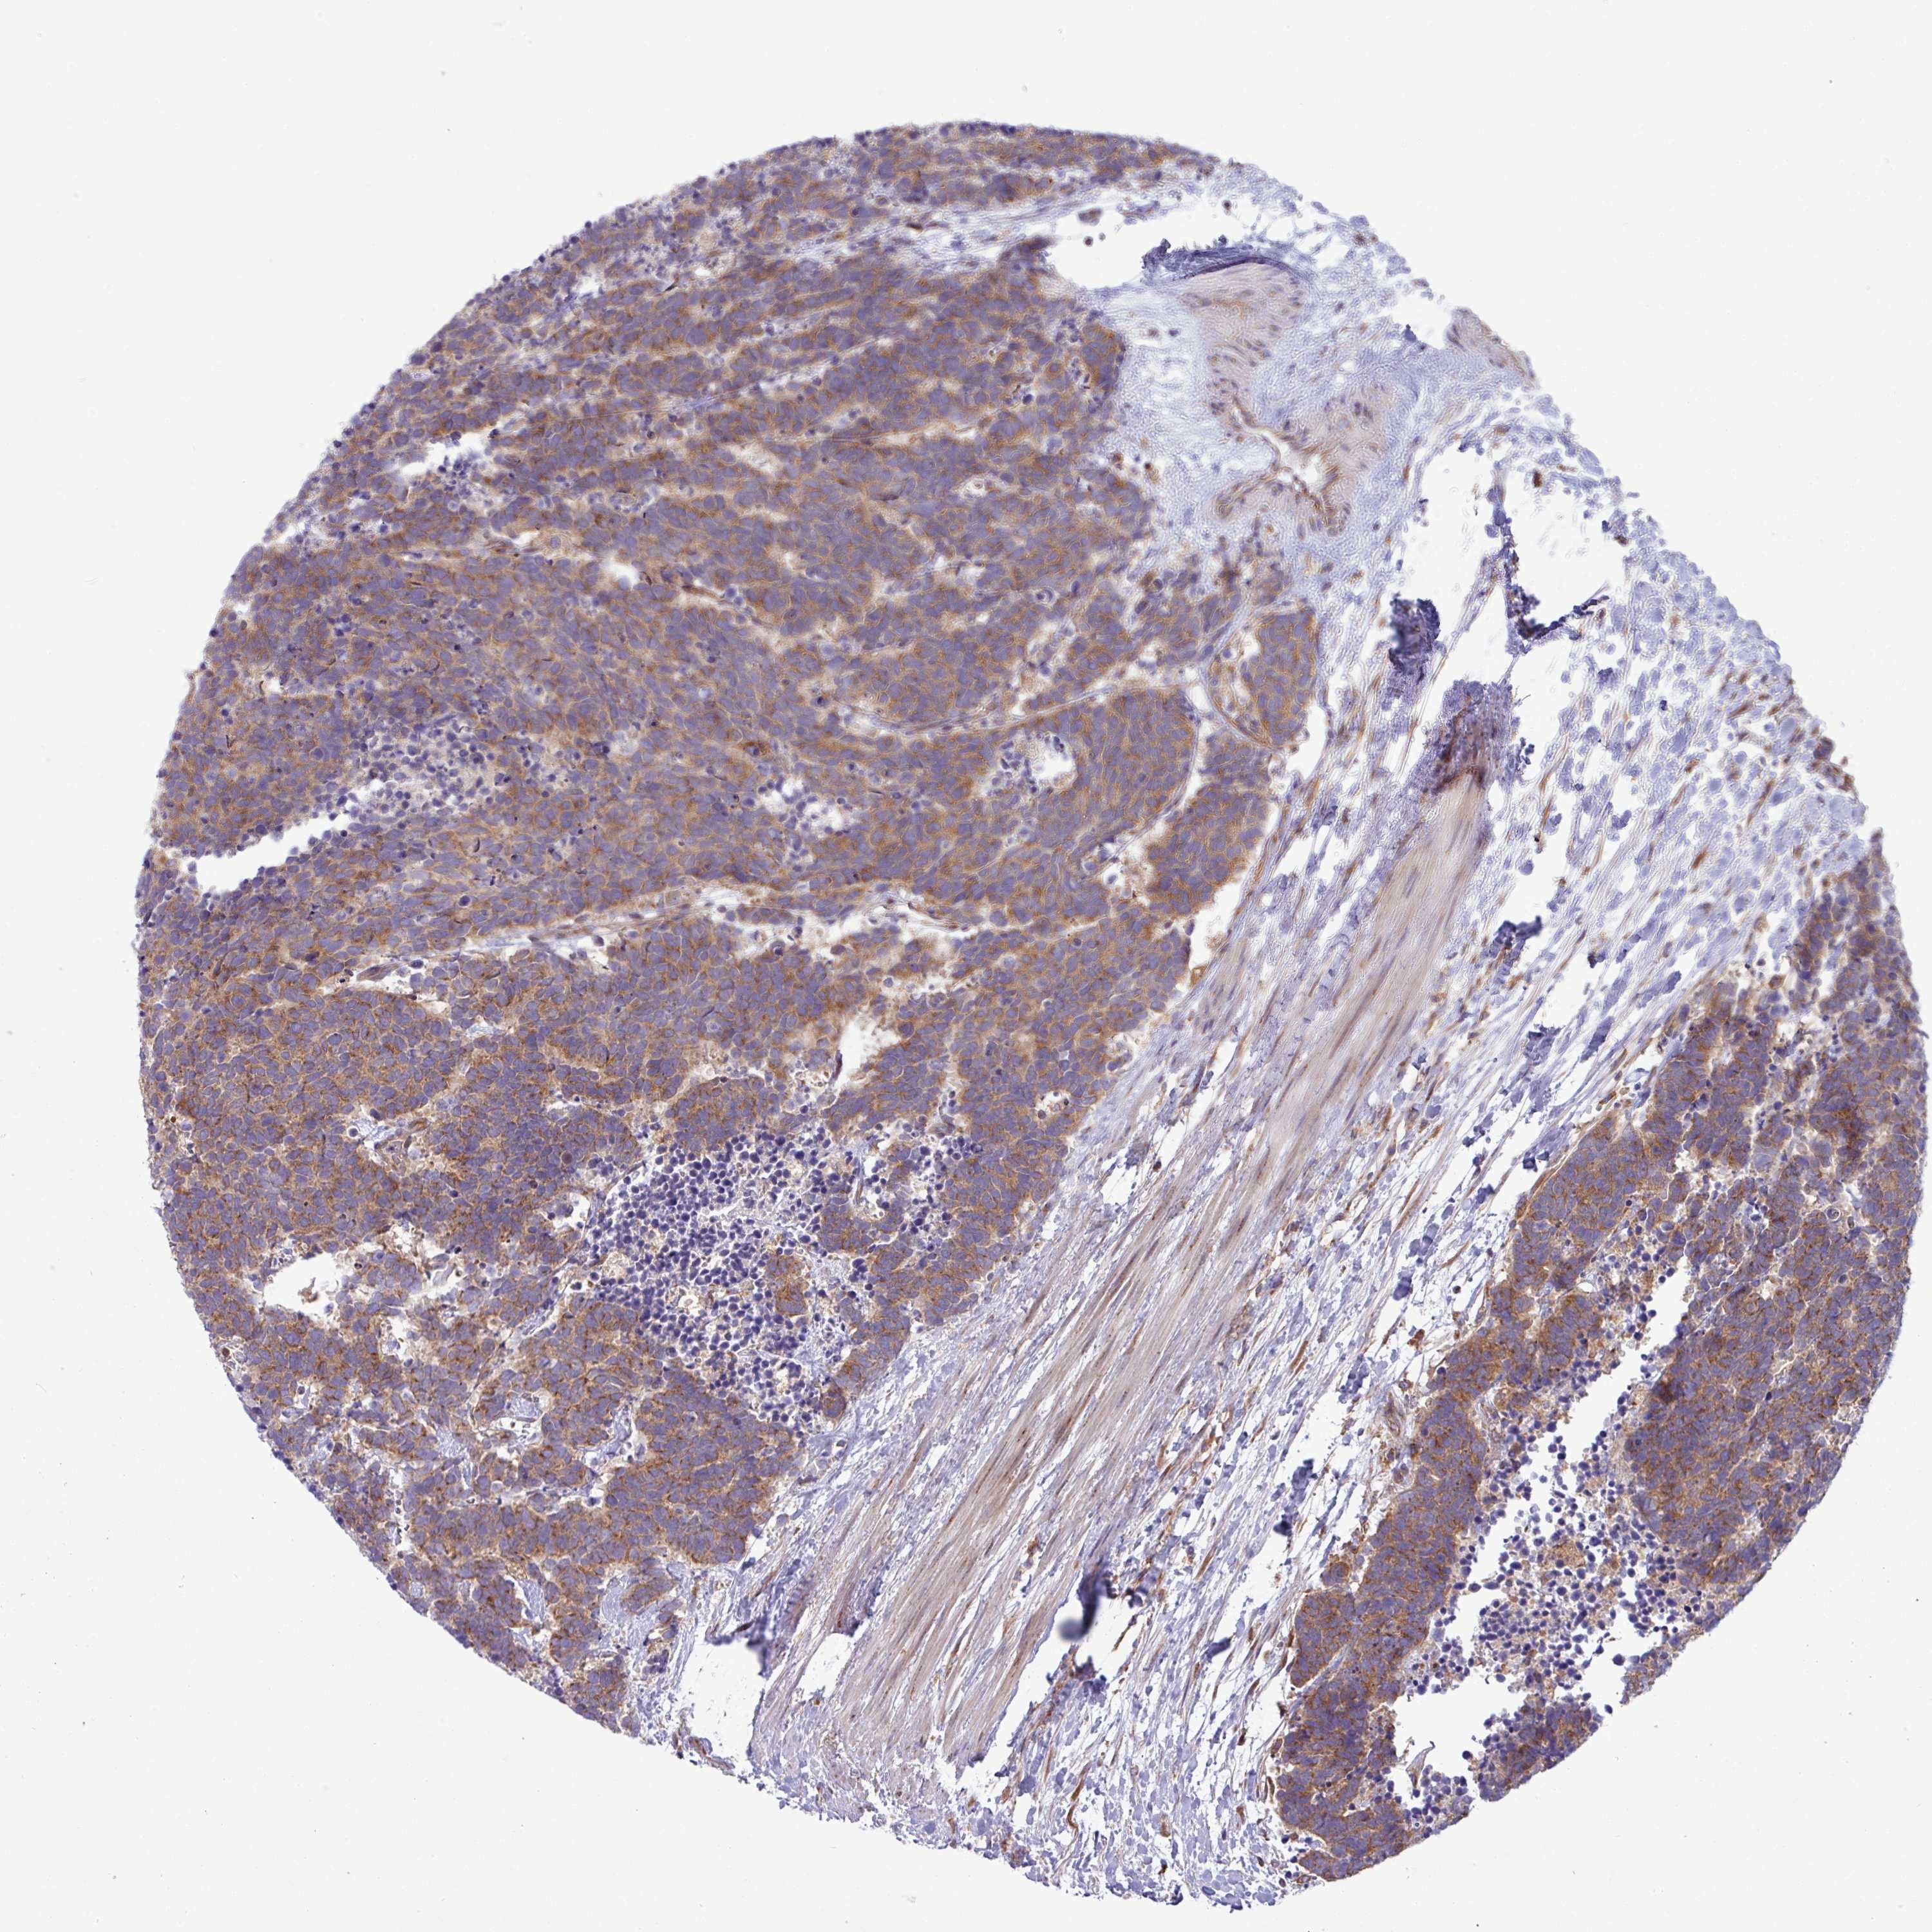

CARCINOID - Protein expressioni

A mouse-over function shows sample information and annotation data. Click on an image to view it in a full screen mode. Samples can be filtered based on level of antibody staining by selecting one or several of the following categories: high, medium, low and not detected. The assay and annotation is described here.

Each image is clickable and will lead to virtual microscopy that enables deeper exploration of all samples and also displays staining intensity scores, fraction scores and subcellular localization as well as patient and tissue information for each sample.

Antibody HPA051077

Staining

High

Intensity

Strong

Quantity

>75%

Location

Cytoplasmic/membranous

Carcinoid, malignant, NOS

Carcinoma, NOS